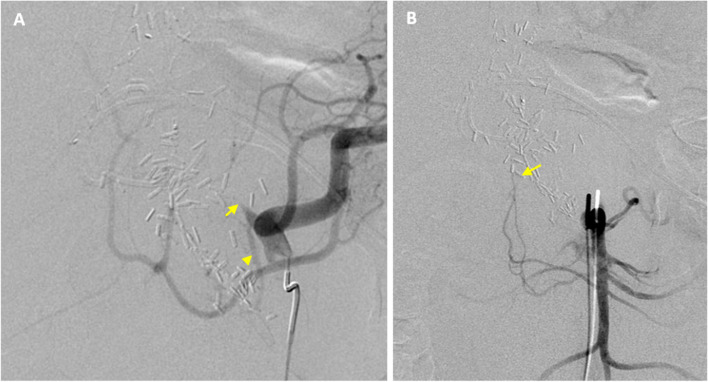

Case presentation: A patient presented with an enlarging hematoma due to bleeding at the gastroduodenal artery HAIP catheter insertion site. Emergent angiography revealed concomitant common hepatic artery occlusion and retrograde perfusion of the GDA via tortuous, diminutive hepatic collaterals which precluded standard antegrade approach. Collateral inflow from the dorsal pancreatic artery was utilized to opacify the right hepatic artery. The segment 5 hepatic artery was percutaneously accessed under fluoroscopic guidance, and microcoils were deployed both proximal and distal to origin of the gastroduodenal artery. The patient remained stable throughout the postoperative period and was discharged after an otherwise uneventful admission. Follow-up computed tomography demonstrated resolution of the hematoma and no bleeding or biliary complication from transhepatic access.